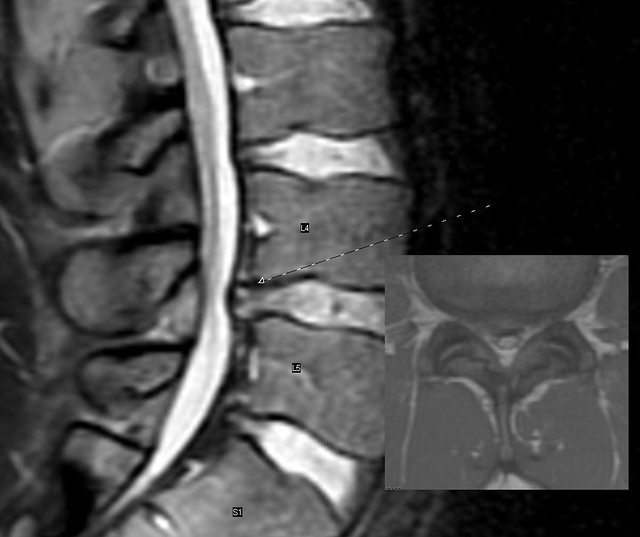

Diagnosis of Herniated Discs

Diagnosing a herniated disc typically involves a combination of physical examinations, imaging tests, and patient history. Healthcare providers will often begin with a comprehensive physical exam, assessing the range of motion, reflexes, and areas of tenderness. Following this, imaging techniques such as X-rays, MRIs, or CT scans may be utilized to visualize the spine and identify any disc protrusions. In some cases, doctors may also use electromyography (EMG) to assess nerve function. Research indicates that MRIs are particularly effective in diagnosing herniated discs, with an accuracy rate of over 90%. It’s important to understand that while imaging can pinpoint the presence of a herniated disc, it does not always correlate with the severity of symptoms. Many individuals with herniated discs lead active lives without requiring surgical intervention, emphasizing the need for a personalized approach to diagnosis and treatment.